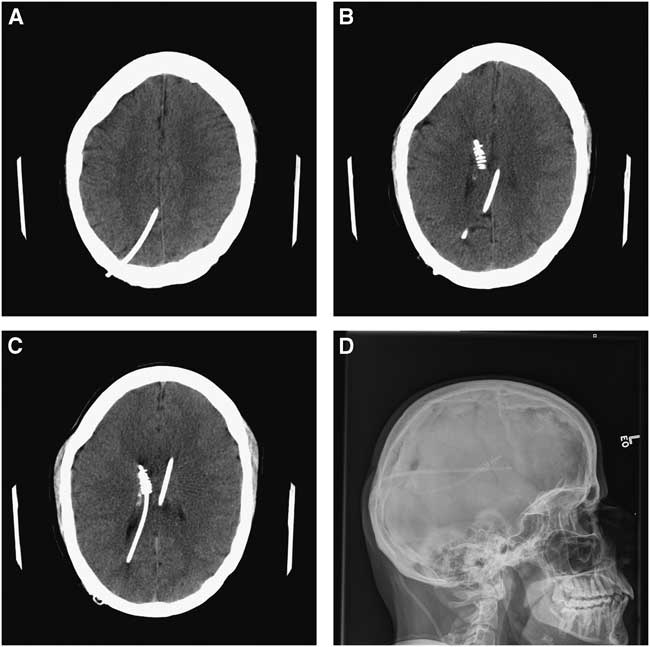

The second patient is a 41-year-old who has spina bifida, with multiple prior shunt revisions. He presented with a 3-week history of fever, chills, abdominal discomfort, and a foreign body sensation in his rectum. On examination, the distal portion of the shunt system was found to be protruding through the patient’s anus. The shunt was externalized and general surgery was performed via laparotomy. A perforation was found at the distal sigmoid/proximal rectum and the fistula was repaired. The patient was treated with intravenous antibiotics. The CSF infection (Enterococcus faecalis and Escherichia coli) persisted on serial CSF samples 16 days later. Imaging revealed a flanged ventricular catheter with retraction of the distal end away from the cortical surface (Figures 3A-3D). This was a retained catheter that was no longer being used but remained within the patient’s right lateral ventricle. Endoscopic removal of the flanged ventricular catheter was performed, followed by placement of a new external ventricular drain.

Figure 3 Patient 2. (A-C) Axial CT scan images of the brain with the retained Portnoy flanged ventricular catheter (Integra Lifesciences Corporation), retracted at its distal end from the cortical surface. (D) A scout X-ray image that demonstrates both the patient’s current standard ventricular catheter as well as the flanged catheter.